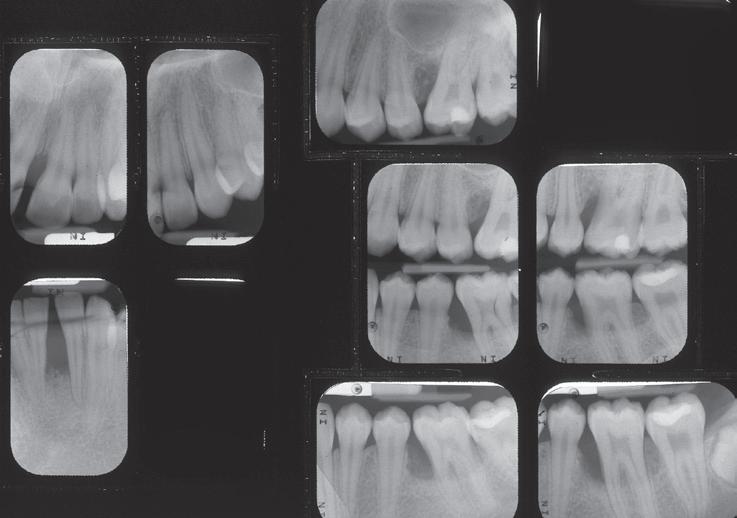

Klinisch was er inderdaad sprake van ernstige problematiek met bij de eerste molaren en de boven- en onderincisieven pockets tot 10 mm en diepe angulaire bot defecten met 50% botafbraak. Gegeneraliseerd is de gingiva ernstig ontstoken met een bloedingsscore van 67% (Afbeelding 3 en 4). Kortom, zeker gezien haar jon ge leeftijd, gegeneraliseerde parodontitis, vergevorderd snel progressief. Het gevolg daarvan was dat we haar direct moesten teleurstellen en aangeven dat een ortho dontische behandeling, zolang er sprake was van een parodontale ontsteking, er voorlopig niet in zat. Eerste prioriteit was nu het bereiken van een parodontaal zo op timaal mogelijke, gezonde situatie.

Afbeelding 4a en b. Röntgenfoto’s Intake (30-11-16)